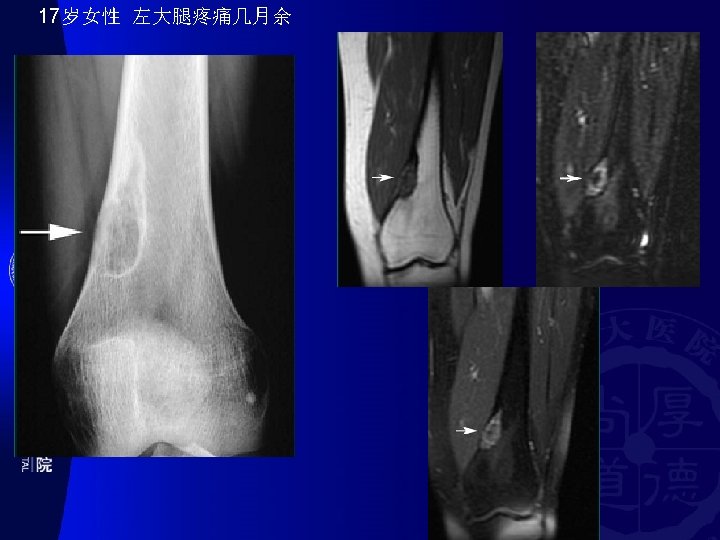

� 骨好� 部位(SITE OF LONG BONE INVOLVEMENT ) (most primary bone tumors have favored sites within long bones; this may provide a clue to diagnosis). Diaphyseal intramedullary lesions: Diaphyseal lesions centered in the cortex: 釉� 瘤, 骨� 骨瘤 尤文氏瘤,淋巴瘤, 骨髓瘤,� �� 构不良,内生� 骨瘤 Metaphyseal intramedullary lesions: 骨肉瘤、� 骨肉瘤、 �� 肉瘤、�� 性骨囊� 、 � 脉瘤� 骨囊� Metaphyseal lesions centered in the cortex: 非骨化性�� 瘤(NOF) Epiphyseal lesions: � 骨母� 胞瘤 (Ch) and 骨巨 � 胞瘤(GCT) Metaphyseal exostosis: 骨� 骨瘤